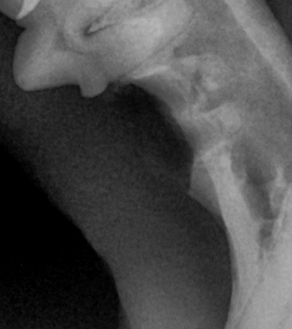

BEFORE

AFTER